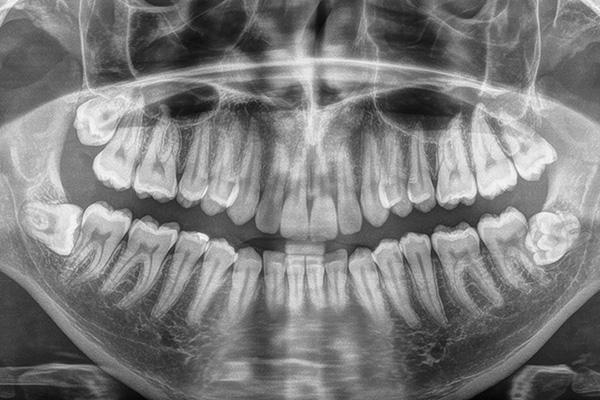

Nos enfocamos en la prevención y cuidado de la salud bucal. Se diagnostica al paciente por medio de una historia clínica completa, toma de radiografías y revisión detallada, valorando si el paciente presenta alguna molestia y enfocándonos en su motivo de consulta.

En esta área nos enfocamos en revisar terceras molares (cordales o muelas del juicio), diagnosticando si es necesario la extracción.

La extracción de las terceras molares es un procedimiento frecuente y normalmente sin complicaciones.